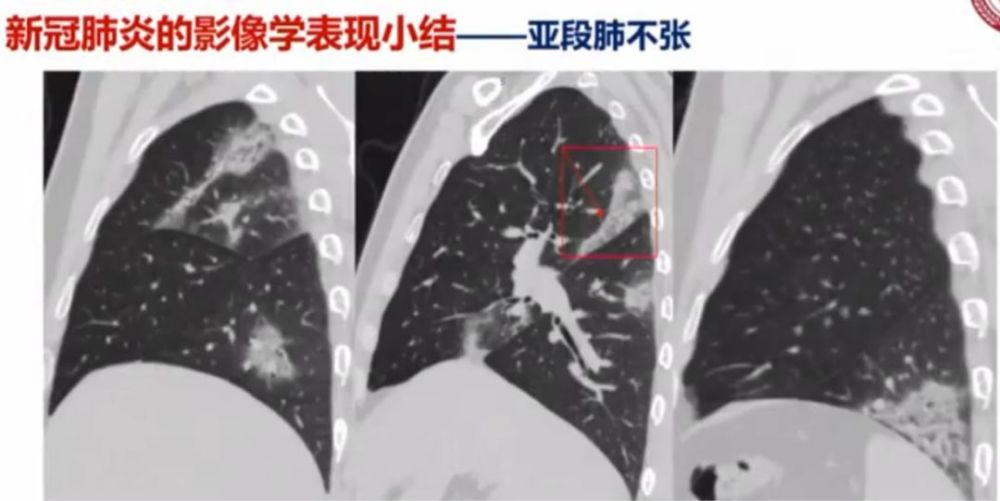

从影像病理学基础看新冠肺炎的ct"三字金律"

新冠肺炎ct早期征象与临床基础及鉴别诊断

新冠肺炎影像学的13种特点,这篇文章为你总结全了!